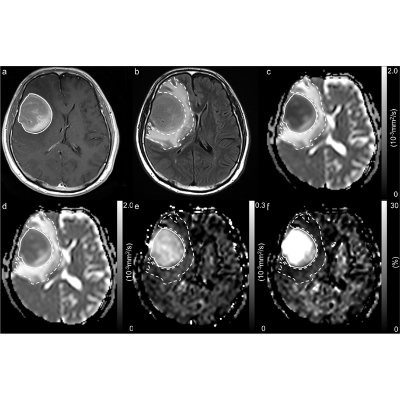

Primary central nervous system lymphoma

Primary central nervous system lymphoma (PCNSL) is a type of diffuse large B-cell lymphoma that specifically affects the brain, spinal cord, leptomeninges, and/or eyes. The exact causes are not fully understood, but research indicates involvement of immunoglobulins binding to self-proteins in the CNS, as well as genetic alterations related to B-cell receptor and signaling pathways. Further research is needed to improve diagnostic methods,...